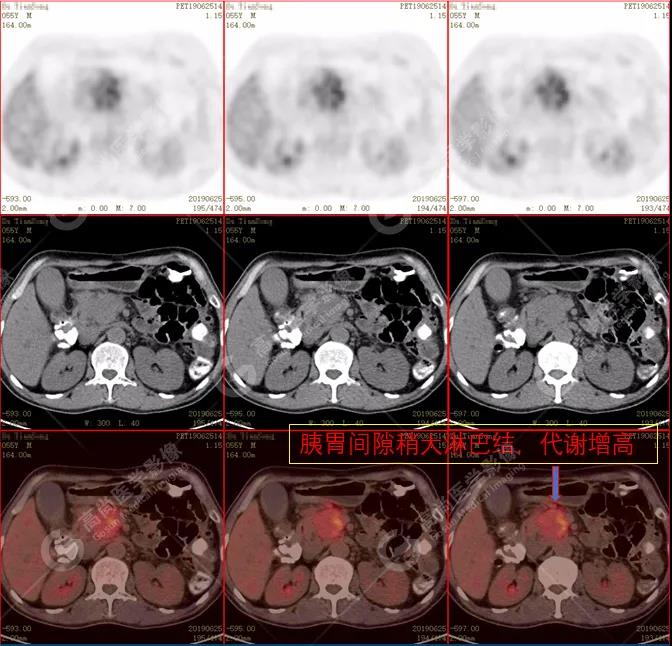

(2)胰周(胰胃間隙)稍大淋巴結,代謝增高。

PET/CT診斷

自身免疫性胰腺炎,伴胰周淋巴結炎性增生。